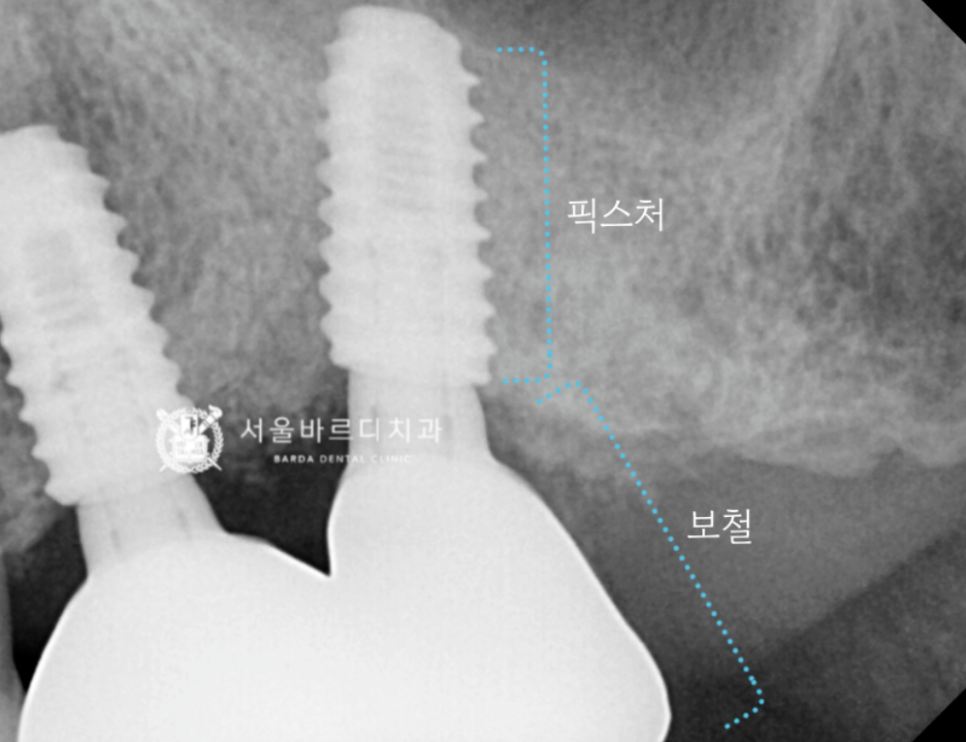

임플란트는 정확히 말하면 치아 뿌리 부분입니다.

230803 픽스쳐 = 임플란트 = 치아 뿌리 부분

때문에 임플란트 1개 가격이 수술비만 포함된 것인지

보철과 기둥 비용까지 포함된 것인지 확인이 필요합니다.